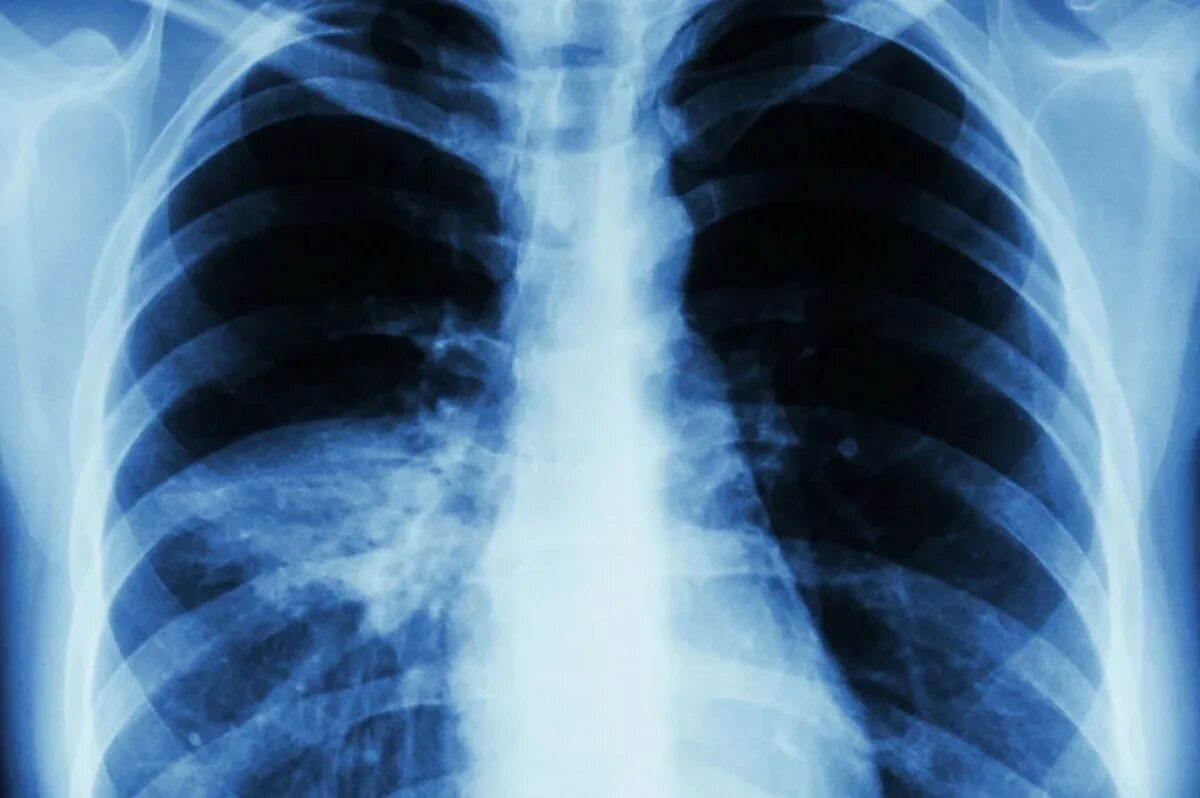

Пневмония – это одно из наиболее распространенных и потенциально опасных заболеваний дыхательной системы. Это воспаление легких, которое может быть вызвано бактериями, вирусами, грибками или даже химическими веществами. Мы часто слышим о ней летом, когда люди переохлаждаются, или зимой, когда простуды и грипп активизируются. Однако пневмония – это не просто «простуда легких». Если ее своевременно не лечить, она может привести к серьезным осложнениям и даже угрожать жизни.

Пневмония – это воспалительный процесс, который поражает альвеолы в легких. Альвеолы – это маленькие воздушные мешочки, где происходит обмен кислорода с углекислым газом. Когда в альвеолы попадают вредоносные микроорганизмы, они начинают активно размножаться, вызывая воспаление, отек и нарушение дыхательной функции.